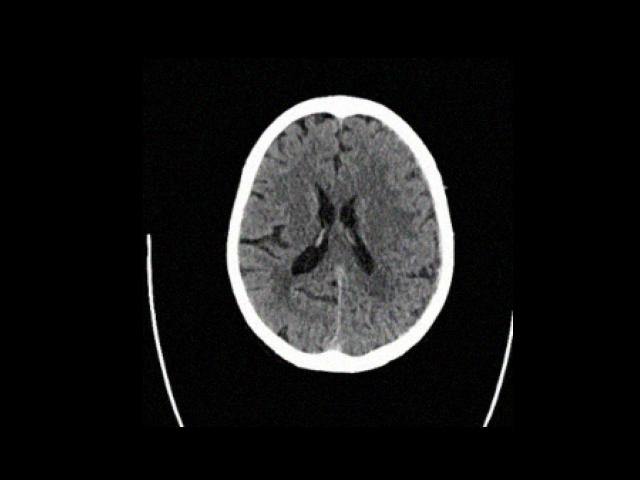

Sample Gallery